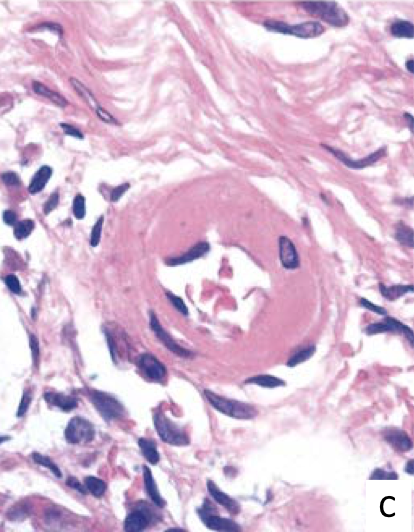

Hyperplastic arterioloscerosis due to malignant hypertension